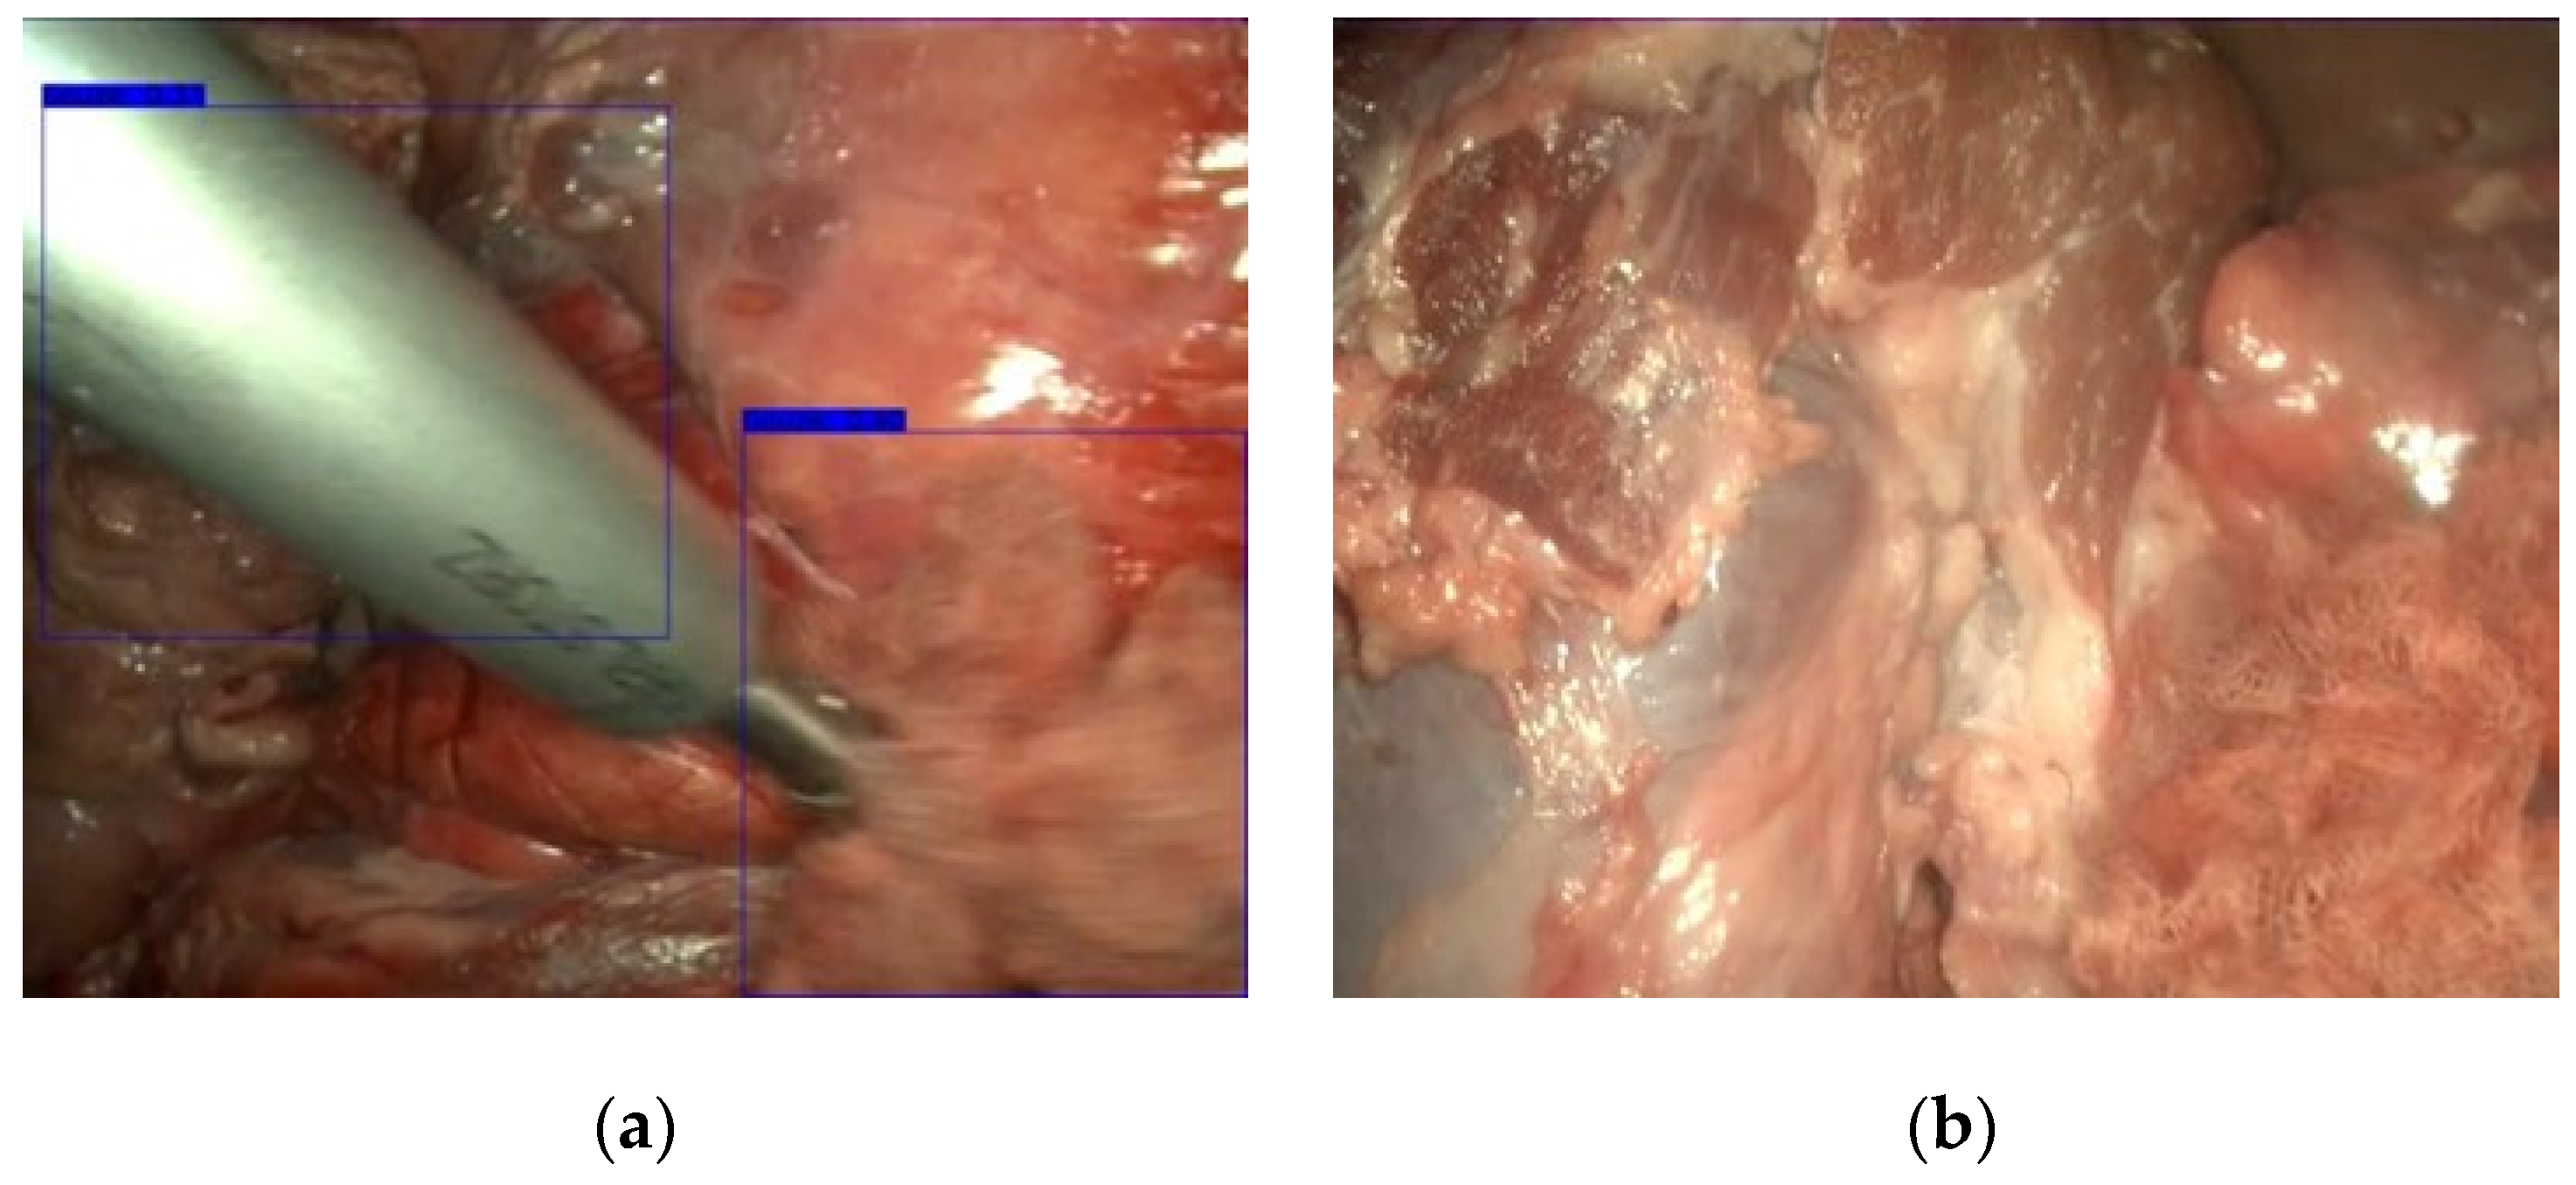

3.1. Gauze Detection